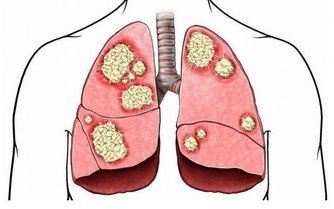

4.促進腸胃健康:每天只要走10到15分鐘,就能有效幫助消化和排便系統。根據研究,多走路還能有效幫助降低女性罹患結腸癌的風險。